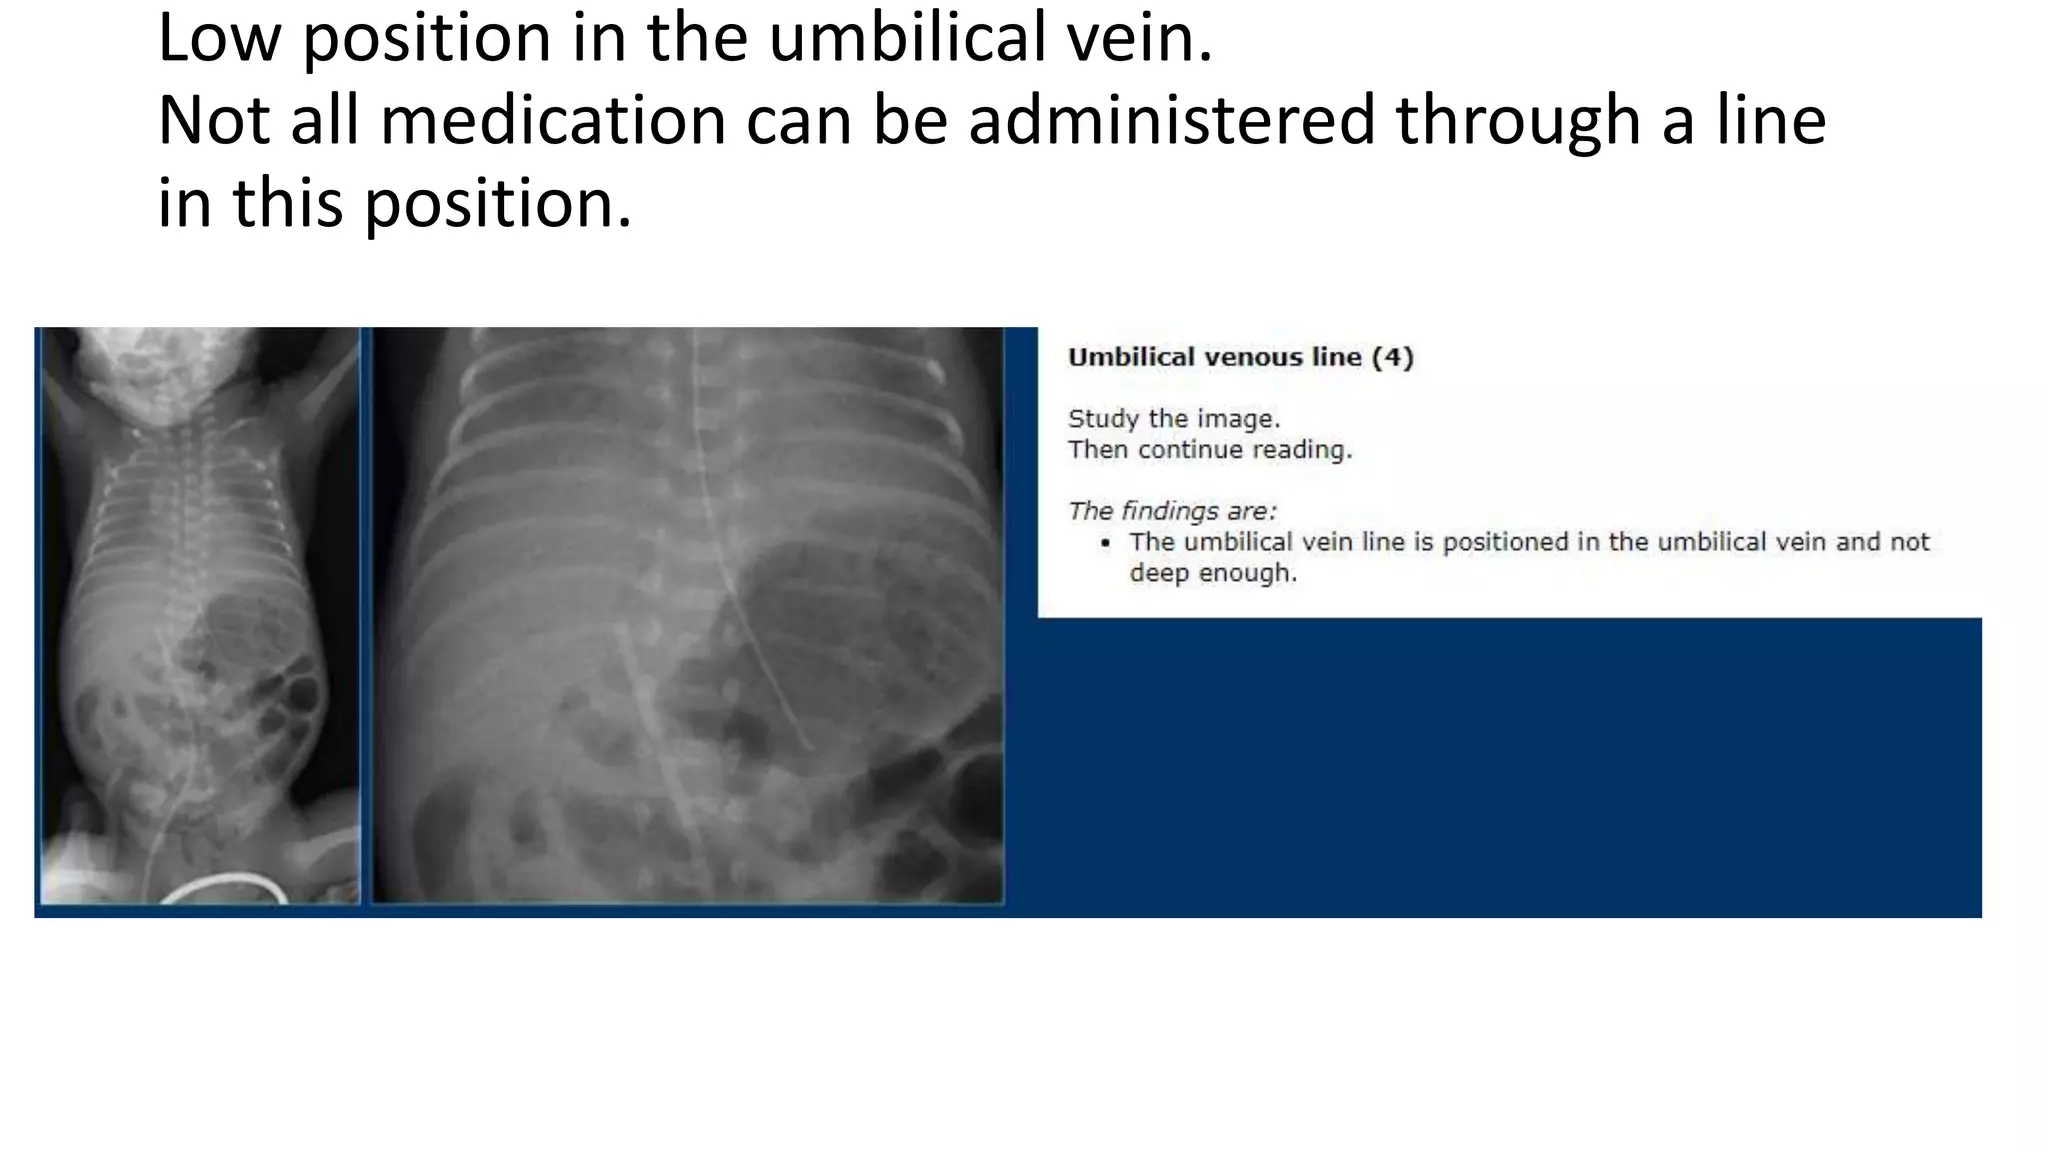

This document provides an overview of neonatal chest x-rays, including when they should and should not be performed, what a normal x-ray looks like, common positions of tubes and catheters, and common causes of respiratory distress in neonates. It discusses the appearance of a normal chest x-ray as well as conditions like respiratory distress syndrome, transient tachypnea of the newborn, meconium aspiration syndrome, and pneumonia. Surgical conditions like diaphragmatic hernia and esophageal atresia are also reviewed.